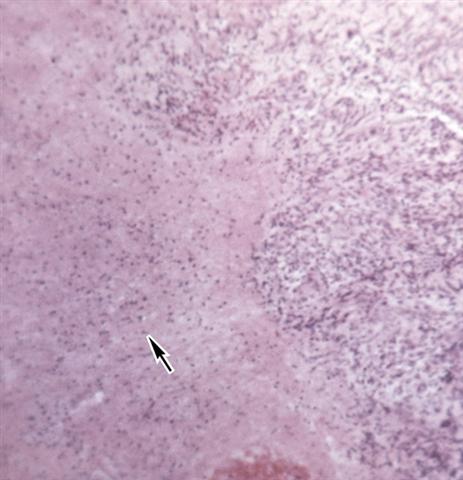

Рис. 14. Микропрепарат слизистой оболочки матки при казеозном туберкулезном эндометрите: в слизистой оболочке матки виден очаг деструкции (указан стрелкой); окраска гематоксилином и эозином; ´100.